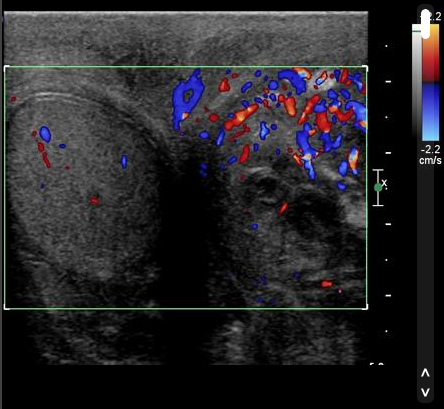

USS is especially useful in patients with sudden onset pain to assess for Testicular Torsion (no flow on colour doppler in many cases) and to assess for Epididymo-orchitis (increased flow in many cases)

Ultrasound 1 Epididymo-orchitis – “Testicular US demonstrates increased vascularity in the left testis and epididymis in keeping with epididymoorchitis. There is also a left sided hydrocele.